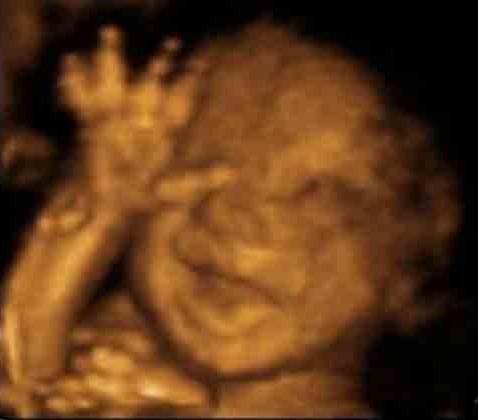

Trên thực tế có vô vàn khoảnh khắc dễ thương của em bé trong bụng mẹ được các gia đình chia sẻ đem đến cảm xúc vui vẻ và ấm áp cho người xem:

Em bé với nụ cười tươi rạng rỡ và gương mặt dễ thương khi nằm trong bụng mẹ.

Bố mẹ em bé chắc hẳn sẽ cảm thấy hạnh phúc khi bắt gặp hình ảnh con yêu giơ tay chào và há miệng cười to trong bụng mẹ.